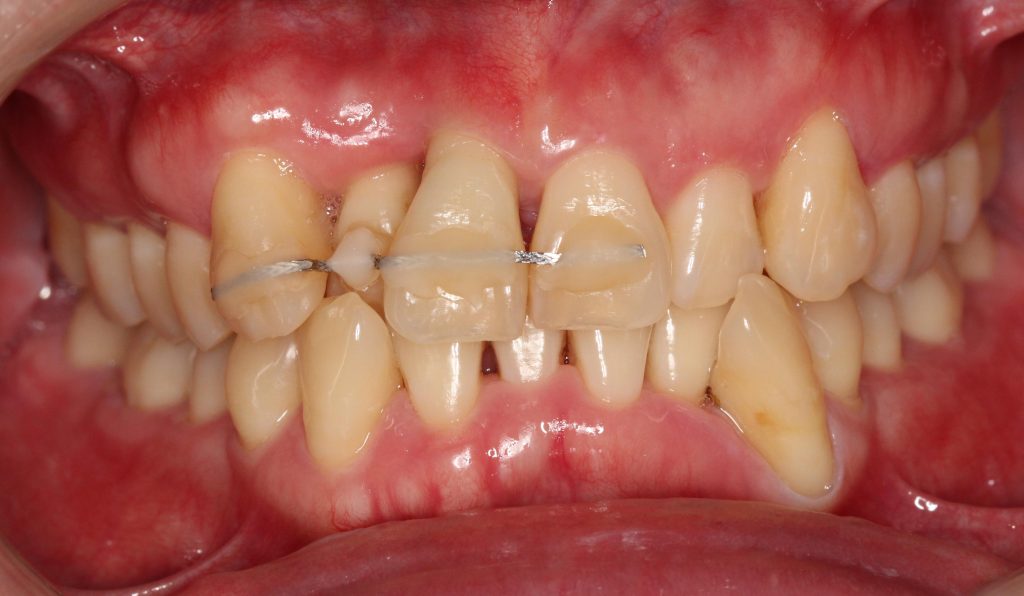

嚴重缺牙的後果? 不管是蛀牙導致的缺牙、退化所致的缺牙、意外造成的缺牙,嚴重缺牙最先會面臨到的問題是「營養流失」,長時間無法正常咀嚼、進食,吸收不佳的情況下,會導致營養不良。 此外,嚴重缺牙會讓口腔上下顎,無法對襯咬合,導致嘴巴無法正常閉合,除了影響美觀,長久下來,也會影響顳顎關節(temporomandibular joint)、咀嚼呼吸系統。 長時間缺後牙的後果? 「缺後牙沒有關係阿,反正看不到,用前面的牙齒咬就好」。這真的是大錯特錯的觀念,長時間缺後牙、錯失黃金治療期,後果,並非想像中的那麼簡單! 「上方後牙區缺牙」,會造成下顎後牙的牙齒往上移,導致錯位咬合,牙脊高度流失、上顎鼻竇腔膨大下墜。之後如果要植牙時,必須伴隨補骨、牙脊增高術或者上顎竇增高術。 「下方後牙區缺牙」,會造成上顎後牙的牙齒往下墜,導致錯位咬合,錯失黃金治療期,會讓牙脊高度、寬度流失,導致缺牙區沒有空間做假牙。 - 假牙的種類 2026.01.19

數位植牙的好處? 不管採取何種植牙治療方式,「4D微創導航系統」牙科技術能夠輔助醫師,在治療時,除了能透過醫師臨床的經驗與技術外,更能精準的控制與判斷病患的所有狀況,降低療程時可能發生的風險,以及減緩術後的不適感。 醫師會在病人的缺牙上,裝上一顆如同「監視器」的機器,搭配「4D動態導航系統」牙科技術,讓醫師在植牙的時候,能夠即時、精準的監測病人口腔骨頭內的狀況。 植牙有黃金治療時間嗎? 植牙的黃金治療期是「越來越快好!」為什麼是「越快越好呢?」最主要是因為牙齒與牙槽骨是相互依存的關係,當缺牙的第一年,骨頭會吸收得特別快,接下來每年以等比的速度吸收。 當口腔內的牙齒,有任何問題或是已經出現缺牙的情況,應該盡快尋求牙醫師的協助!進行治療與骨頭重建的需求評估,已避免增加重建的困難度,甚至無法治療。 到底適合「植牙」,還是要做利用兩邊牙齒做「牙橋」,最終還是需要經過醫師的專業判斷。 如何在茫茫醫海中,尋找適合的植牙醫師? 「一般牙科、贋復補綴科、口腔顎面外科、牙周專科」現代人很喜歡上網做功課,但想要找植牙醫師時,卻不知道從何尋找到適合的植牙醫師。 其實,能夠提供患者專業植牙技術的醫師,通常會受過「贋復補綴科、口腔顎面外科、牙周病科」這3大科的專業訓練。 擔心花錢後植牙出現問題又無法處理,如果長期看診的牙醫診所沒有相關的專業醫師,可以請醫師幫忙轉介。 另外,也可以挑選幾位自己喜歡的醫師,進行面診諮詢,找出最適合的醫師。最後,與醫師充分的溝通、配合也是植牙成功與否的重要關鍵。 植牙的步驟 植牙的流程大致可以分為幾個階段:資料蒐集、資料分析與重建理想牙位、植牙手術與植牙臨時假牙製作,以及最後最重要的植牙假牙製作。 植牙諮詢的第一步「資料蒐集」 資料蒐集、分析: 先利用口腔掃描機、臉部掃描儀、X光片、斷層掃描等,蒐集病患口腔整體環境、牙齦、骨頭的臨床資訊,以及紀錄顳顎關節與咬合的情況。 植牙手術 植牙手術:在經過專業的醫療團隊,進行術前評估後,以及擬定個人化的治療方針後,就會進入植牙手術的步驟,手術的步驟,會先進行牙齦翻瓣、鑽孔、植入人工牙根、縫合、拆線等。 不少人聽到上述步驟,或許已經頭皮發麻,專業的醫療團隊在治療的過程中,會搭配「舒眠麻醉」治療,能夠降低病患在過程中的不適感與恐聚感。 而通常人工牙根的癒合期大約需要6-12週的癒合,待癒合後才會進入「植牙臨時假牙製作」的製作。 植牙永久有效? 植牙有保固期 ? 「植牙成功後,就一勞永逸了嗎?就不用與醫師相見了嗎?」植牙它是鈦金屬釘子,植入骨頭癒合後,它不會蛀牙。但是,植牙周圍的牙肉跟骨頭,如果不妥善保養的話,還是會導致牙周病的發生,就是所謂的植體周圍炎。 植牙上方接出的牙冠,就好比買一台車,牙冠用久了,就如同車子用久了,零件、螺絲依舊會出現損毀的狀況,所以定期的回診保養追蹤是相當重要的。 通常植牙牙套完成後,至少半年回診一次,讓牙醫師檢查確認植牙附近牙齒沒有累積牙箘斑牙結石、植體周圍牙肉沒有發炎化膿,中間固定的螺絲沒有鬆動、牙套沒有破損、咬合狀況穩定等。 此外,患者必須維持良好的口腔清潔,可以參照之前我介紹的牙齒清潔方式,來保持好的口腔衛生、少抽菸等,如此搭配定期的回診檢查,可延長植體壽命。 植體的構造 植牙的治療過程很漫長,很多病患最常問的是「嘴巴內裝上的到底是什麼東西?」 今天的「植牙芯教室」就要帶你來認識「植牙整體的構造」(Dental implant) 口腔內的植牙由上→下依序是:牙冠、支台體、植體。 牙冠:又稱假牙冠、牙套,它是提供如同真牙的咀嚼功能,並且恢復美觀,永久性的牙冠最常見的材質為:全瓷、金屬合金、瓷熔合金屬。 支台齒:連接牙冠與植體的延伸部分,在中間點扮演重要角色,因為它必須要支撐牙冠的咬力,同時又要提供牙肉健康的生長環境,所以專科醫師在安裝時,必須依造病患口腔的狀況「客製化」的設計,ˊ尋找最適合的形狀、大小與角度。 植體:置入於缺牙的牙槽骨中,功能是取代原有的「牙根」,負責穩固牙齒的地基,目前最常見的植體材質為純鈦、鈦合金。 植牙x牙冠材質 對於越來越講求美觀的現代人來說,花錢植牙,當然希望它能美觀性與功能性兼具。 今天的「植牙芯教室」就要帶你來認識「牙冠材質」 目前,市面上永久性的牙冠最常見的材質為全瓷、金屬合金、瓷融合金屬 。 1.全瓷牙冠:材料有氧化鋯、強化玻璃瓷,不需要使用金屬,材質與人體的生物相容性高,同時具備高硬度的特性、高耐磨、耐高溫。在外觀上,呈色自然如同真牙,美觀性極佳。 2.瓷融合金屬牙冠:由於合金的成分複雜,若是高貴金屬的成分(黃金、白金)不夠高時,在口腔高溫潮溼的環境下,金屬容易腐蝕,導致表面粗糙,使牙菌斑難以徹底清潔,就容易造成牙齦發炎,並且染色,長期在美觀上、實用性都難以符合,對於外觀講求自然的病患。 3.金屬合金牙冠:由於整體採用金屬製作,所以不容易破裂、折斷,但是外觀呈現金屬色,所以當張開口時,便能夠一眼看出假牙的位置,如果使用金屬和金的牙冠,建議使用高貴金屬成分較高的材質。 植牙前的注意事項 想要提高植牙治療成功率,醫師與病患互相配合很重要,從術前的資料蒐集、評估與診斷,依據病人的情況,給予專屬的治療方針,從術中的治療過程,到術後的維護都非常重要,先來談談植牙前要注意那些事情。 1.保持口腔衛生:口腔清潔是植牙成功的最大關鍵 2.降低煙癮:抽菸會影響植牙的成功率,應該要盡量避免,如果能夠戒菸成功,更能提高植牙的成功率。 3.持續服用慢性病藥物:如果有在服用慢性病(高血壓、糖尿病等),在術前的諮詢,務必完整提供用藥歷史給醫師。 植牙後的潔牙步驟-工具篇 「植牙疏於潔牙與保健,百萬台幣立刻船過水無痕。」這是血淋淋的案例,真的不要以為,植牙完成後就一勞永逸。 術後的口腔清潔與維護非常重要!非常重要!非常重要!因為植牙的「使用壽命」,有非常大的關聯性。 植牙維護有三寶:牙刷、牙間刷、牙線 牙刷:可以選擇自己習慣的刷頭,或者選擇刷頭短小、刷毛軟硬適中的牙刷 牙間刷:當牙齦萎縮、牙縫變大時,應該選擇適合牙縫大小的牙間刷,用來清潔齒間的縫隙、牙套底層的牙菌斑與食物殘渣。 牙線:使用超級牙線,來清潔牙橋下的支柱牙部分。 漱口水、沖牙機等,這些只是輔助工具,千萬不能把它當作正規的潔牙器材。 植牙後的潔牙步驟-清潔篇 植牙的清潔方式。 首先:使用牙刷在假牙與牙肉的交界,採用刷牙法,來回輕刷至少10次。 接著:使用牙間刷,輕貼牙齒的表面,進行前後清洗,按照同一個方式,從舌側進入,輕貼牙齒表面,再做一次清潔,每次動作至少5次。 最後:使用大約45CM的牙線,可以使用穿引器的輔助,深入牙橋底下做清潔,每次動作至少5次。 植牙後的潔牙步驟-電動牙刷VS.一般牙刷 「做完牙套後可以用電動牙刷刷牙嗎?潔牙工具怎麼選?」上一篇,談了植牙的清潔方式,究竟植牙到底該不該用電動牙刷?答案是「可以」。 科學研究指出,使用電動牙刷,能更深入清潔到牙縫與牙齒倒凹處,尤其對於手部協調性沒那麼高的人,以及牙齒排列凌亂者,在清潔上能夠達到更好的效果。 刷頭的選擇:一樣要以刷頭小、刷毛軟硬度適中的刷頭,建議每1-3個月,或者外觀出現彎曲變形,刷頭就必須更換。千萬不要因為刷頭,比一般牙刷貴捨不得更換,反而會讓潔牙效果打折扣。 潔牙方式:電動牙刷與一般牙刷的潔牙方式的差異在於,電動牙刷只需要將刷頭輕放在單顆牙齒上,讓刷頭在牙齒與牙肉的交界處轉動,手不需要來回移動刷頭。但是千萬不要重壓,施壓過多的力道在牙齒上,反而對於牙齦是種傷害。 另外,不管使用電動牙刷或一般牙刷,都一定要使用牙線、牙間刷,來清潔牙齒與牙齒間的鄰接面,確保牙菌斑被清除。 潔牙時間:三餐飯後,30分鐘內如果能夠潔牙是最好的,如果無法達到,睡前徹底的潔牙是最重要!另外,潔牙時一定要有耐性,不要為了節省時間,隨便刷2.3下就結束。 如何選擇:預算、操作與攜帶方便度為首要考量,而且選擇具有「經濟部標準檢驗局」檢驗合格的產品,設計不良的電動牙刷,可能會造成口腔受傷。 植牙後的術後照護 植牙的最終成功與否,術後照顧真的非常重要!務必遵從醫囑,以下是照護的重點。 1.冰敷:術後1周,依舊會有些許的腫脹與輕微的瘀青,在48小時內,建議患者可以冰敷,在臉頰外側冰敷15-20分鐘,休息10分鐘,重覆動作到48小時。 2.不要泡溫泉、熱水澡,以及從事游泳與劇烈的運動。 3.飲食方面:初期還是會建議以流質、軟度高的食物為主,過燙、過冰的流質食物則不宜,應該避免食用過燙、辛辣、含有酒精成分刺激性的食物。 4.降低菸癮:為了讓植牙的傷口能順利恢復,醫學上皆有文獻記載,術後1周必須降低菸癮。 5.定期回診:植牙完成還是必須定期回診,讓醫師確認傷口、口腔健康的情形。 根據手術療程的不同,每一項術後的照護方式也有所差異,未來會跟大家分享與討論。 植牙後就能一勞永逸,不會有牙周病? 大多數的病患都知道,植牙前要先把牙周病及其他口內問題處理好,以降低口內細菌數量,才能夠進行植牙,但是很多病患以為,植牙成功,同時也能跟牙周病永久說再見,這觀念完全不正確。 簡單說「牙周病」是牙齒的周圍骨頭受到細菌的破壞,所造成的結果。因此,在植牙後,如果植體周遭的牙肉與骨頭,沒有得到妥善的清潔與照顧,還是會造成口腔內細菌的滋生,一樣會導致牙周病的發生。 植牙後,是不是也跟敏感性牙齒Say Bye Bye 一般所說的「敏感性牙齒」真正的學名是「牙本質知覺敏感症(Dentin Hypersensitivity)」會造成敏感性牙齒,主要原因是在於牙齒外層的琺瑯質被磨耗後,失去保護的功能; 或是牙齦萎縮牙根裸露時,都會造成牙本質內的神經小管暴露,當受到冷熱、吹氣、和壓力等刺激下,所產生的神經疼痛不適感。 植牙後,重建的人工牙冠內沒有神經,所以不會有敏感性牙齒的發生。然而,其他的自然牙齒,不會因為植牙而受到改變,當琺瑯質被破壞時,依舊會造成牙齒敏感性的問題。 骨質疏鬆的人適合植牙嗎? 「骨質疏鬆」有越來越年輕化的趨勢,除了因為年齡的增長之外,身體未獲得適當的保養也是元兇之一。如果是輕微的骨質疏鬆,只要適當的補充鈣質,想要植牙依舊沒有問題!整體還是必須交由專業醫師評估。 「骨鬆患者」,尤其是有在服用高劑量或施打抗蝕骨作用的藥物,是會影響植牙的成功率。原因在於,大多數的抗骨質疏鬆藥物,含有雙磷酸鹽,會影響骨骼細胞修補的功能,讓顎骨無法修復。所以如果有服用相關藥物,植牙前一定要告知醫師。 我是高血壓患者,能夠植牙嗎? 在高血壓控制好的前提下,是可以進行植牙手術的!正常的血壓是指收縮壓120/舒張壓80mmHg,當血壓偏高時,會增加手術中的出血狀況,提升手術的複雜度,甚至會提高手術後的感染率。 很多高血壓患者會服用「抗凝血藥物」。「抗凝血藥物」可能會在手術時,出現傷口流血不止的問題,所以醫師在進行植牙評估時,一定要讓醫師了解自身的慢性病史與用藥,並且盡可能尋找能提供詳細治療計畫,以及擅長微創植牙手術的醫師,降低植牙的風險。 我是糖尿病患者,能夠植牙嗎? 糖尿病患者與高血壓患者,都是在控制良好的前提下,能夠完成植牙手術。由於糖尿病控制不良的患者,細胞修復的能力與免疫系統,跟正常人比起來比較低,相對的牙周組織再生能力、傷口癒合情況也比較差。 所以想要植牙,必須同時與新陳代謝科醫師與植牙醫師相互合作,穩定血糖。除此之外,糖尿病患者也應該養成良好的口腔保健習慣,在經過醫師的專業評估,提供完善的治療計畫。 糖尿病與牙周病的關係? 「牙周病已經被列為糖尿病的併發症之一」前面談到「只要控制好血糖」依舊能夠植牙。我們也提到植牙前,一定要把牙周病控制住。今天我們就來談談「牙周病與糖尿病控制不良的關係」。 事實上,糖尿控制不良的病患發生牙周病的機率是正常人的3倍。最主要的原因,口腔細菌量會比正常人多,由於免疫系統比較差,更容易受到感染,所以傷口的復原能力也較低。 一旦糖尿病控制不良者得到牙周病時,病程也會跟著加速,骨頭被破壞與受損的速度也會加快。並且,因為身體長期發炎,將會導致血糖更不易控制。 癌症患者適合植牙嗎? 「癌症已經連續多年佔據國人10死因的首位」而癌症到底能不能進行植牙手術呢?首先,醫師會先了解病人的癌症種類與期數,以及過去的病史、治療史、用藥史,經由病人提供的資料,來做精準的判斷。 癌症的放射治療、免疫抑制等是會影響到傷口的癒合,治療上會使用到,抗骨吸收藥物 (antiresorptive agents)與抗血管生成藥物(antiangiogenic agent)等,都很有可能增加顎骨壞死的風險。另外,頭頸部經過放射線照射後,也會造成骨細胞的活性降低。 而且病人在接受化療、標靶藥物時,也會因為治療後,免疫力降低,細胞修復能力變弱,如果在治療期間,或是在治療後,想要做植牙,都應該先找醫師進行評估身體各項數值,以提高植牙成功率。 懷孕期間能夠植牙嗎? 雖然植牙是一個小手術,但是通常醫師都不會建議準媽咪們,在這時候進行植牙手術,首先,因為植牙是必須照X光檢查,在懷孕期間,應盡量避免暴露在輻射線下。 同時植牙必須經過麻醉的步驟,雖然麻藥會經由尿液排除體外,但大多數麻藥都含有「血管收縮劑」的成分,在治療過程中引發的加倍焦慮,可能會造成者子宮提前收縮的風險。所以會建議想植牙的準媽咪,產後再進行植牙手術。 產後、哺乳期植牙注意事項 「醫師,我正在哺乳期能植牙嗎?」在懷孕期間,就算已經完成第一階段的植牙手術,醫師為了保護母體與胎兒,會直接將療程暫停至產後,但是女性「產後要多久才能植牙?」、「哺乳期能植牙嗎?」成為許多媽媽最常問的問題。 事實上,女性產後的身體狀況恢復到一定的程度,就能夠進行植牙。而為了擔心麻醉藥或是抗生素、止痛藥分泌到母乳,加上每種藥物的半衰期不同,通常會建議,服用完最後一次藥物,在相隔24小時後,才進行哺乳。 服用健康食品是否會影響植牙 「維他命C、B群、魚油、銀杏、補鈣產品...」各式各樣的保健食品有吃有安心,很多病患到了診間,最常問我的問題之一「醫師,我有在服用各類的保健食品,會影響植牙嗎?」 事實上,需要看服用保健食品萃取的成分而定,不是所有的保養品食品,都會影響植牙的。如果營養品中含有「抗凝血作用」成分的保健食品,例如:銀杏、紅花。會建議在術前1周暫停服用。 雖然,適當的服用保健食品,確實有益於健康,但是在進行植牙評估時,還是務必告知,讓醫師做更正確的評估。 植牙要局部麻醉還是全身麻醉? 「植牙到底要全身麻醉,還是局部麻醉?麻醉的方式有哪些?差異性、有沒有後遺症?」許多病患都會有相同的疑問,從今天開始,一連串的文章來解惑。 其實,植牙手術跟一般口腔治療的方式一樣,能夠在病患清醒情況下進行治療,醫師通常會使用局部麻醉藥內含少比例血管收縮劑(Epinephrine),針對病人的手術內容,與治療所需的時間,給予準確的麻醉劑量。 由於大部分的局部麻醉藥,含有血管收縮劑,之前文章有提到高血壓的患者,必須在做治療諮詢時,提供用藥史與血壓控制情形,並且在手術當天,都應該接受血壓的測量,已確定用藥的安全性。 植牙的成功率?植牙失敗怎麼解?植牙的後遺症? 「植牙能100%成功嗎?植牙後是不是就再也不用回診?當植牙開始出現問題時,怎麼辦?植牙失敗後該如何治療?」這些問題是現在病患在選擇植牙時,很重要的考量。 「植牙成功率及植體壽命的長短」其實,最重要的是取決於醫師、病患有沒有合作無間,醫師與病患都應該在治療的過程中,扮演好彼此的角色,才能在植體成功骨整合後,延長使用的壽命。 病人,在諮詢時,要確實的將藥物史、病史提供給醫師。在治療期間,遵照醫囑、落實口腔衛生,並且在術後定期回診。此外,當植體出現任何情況時,必須立刻尋求醫師的協助「及早發現、及早治療」。 醫師,在技術、經驗上必須給予病患精準個人化的治療方針,並且選用大品牌的植體、生物醫材,提高治療成功率。同時,隨時吸收醫療新知,並將它運用,讓病患得到最好的治療。 上述都是植牙成功不可或缺的關鍵之一。 植牙後出狀況x牙冠瓷破裂 「植牙後出狀況怎麼辦?」 就如同之前所說,植牙就像是一部車子,用久了零件會出現受損的情況,要聊「出狀況怎麼辦?」就要回歸問題的根源來對症下藥,接下來,我將針對「植牙後常見的幾大狀況」來做詳細的說明: 牙冠瓷破裂:可將假牙取下,送修補瓷以回復美觀及咬合功能。因為牙科材料學的進步,新式二氧化鋯牙冠 (Zirconia),幾乎不會有破裂的狀況,這也是目前牙冠材質中,在品質與美觀上的表現,都擁有較高的穩定性。專業的贋復醫師在修復之前,會先把連接體跟牙冠中間的隙縫清潔乾淨,讓植體免於細菌感染的風險。 植牙後出狀況x植體配件的鬆脫、受損 「植體配件的鬆脫、受損」,之前的植牙芯教室,我們有介紹,牙冠與支台齒內含有各種不同的小零件,當植體用久了,零件開始出現狀況,該如何處理? 要談到該如何處置之前,要先了解,為什麼會發生「植體配件的鬆脫、受損」的狀況,大致可以把原因歸類為:零件壽命、植體長期咬合受力。 病患完成植牙後,在每半年的定期回診,牙醫師都會針對這些細部零件做確認,確定是否有鬆脫或晃動的情形出現。 一旦出現螺絲的鬆脫情況,沒有及時治療,螺絲就會斷裂在植體內,而要從植體內,將斷裂的螺絲取出,是件複雜又具高風險的療程,必須由經過專業訓練的植牙贋復科醫師來做處置,在往後的文章,將再做更詳細的說明。 植牙的麻醉方式有哪些? 「舒眠麻醉、全身麻醉、笑氣麻醉」這是目前大家在搜尋資料時,比較容尋找到的關鍵字,今天就來簡單介紹,這些麻醉的專有名詞。 舒眠麻醉:目前贋復科醫師最常使用的麻醉方式,屬於淺層麻醉,能夠讓病患在放鬆的情況下進行治療,也能夠降低局部麻醉的用藥量,關於「舒眠麻醉」接下來會一系列的介紹。 全身麻醉:屬於深度麻醉,麻醉藥的劑量會讓病患意識消失,而且無法自主呼吸,術後的恢復期較長,必須要在開刀房內進行。 笑氣麻醉:主要是用來鎮靜,而非麻醉,有些病患在做口內局部麻醉時,依舊會感受到看牙的緊張感,因此,有些醫院或診所,會備有笑氣設備,幫助病患在局部麻醉時,能夠鎮定。 植牙的評估要件懶人包 Q:缺牙會影響到那些層面? A:身體、心理都會受到影響,長期缺牙會讓導致「咬合障礙」 Q:到底要植牙,還是要做假牙? A:需要經過醫師的專業評估與判斷,「假牙」與「植牙」各有優、缺點。 Q:幾歲適合植牙? A:只要經過牙醫師臨床的評估,不管是25歲較年輕的缺牙病患,或者80歲的族群都能。 Q:如何在茫茫醫海中,尋找適合的植牙醫師? A:專業植牙技術的醫師通常會受過「贋復補綴科、口腔顎面外科、牙周病科」3大科的專業訓練。 Q:怕痛的人,如何進行植牙手術? A:現在也出現了「舒眠治療」,讓患者在治療上,大幅減低焦慮感。 Q:我是高血壓患者能植牙嗎? A:在高血壓控制好的前提下,是可以進行植牙手術的! Q:骨質疏鬆的人適合植牙嗎? A:如果是輕微的骨質疏鬆,只要適當的補充鈣質,想要植牙依舊沒有問題。 Q:癌症患者適合植牙嗎? A:在癌症治療期間或是在治療後,想要做植牙,都應該先找醫師進行評估身體各項數值,以提高植牙成功率。 Q:懷孕期間能夠植牙嗎? A:植牙必須經過麻醉的步驟,所以想植牙的準媽咪,產後再進行植牙手術。 Q:服用健康食品是否會影響植牙? A:需要看服用保健食品萃取的成分而定,不是所有的保養品食品,都會影響植牙的 舒眠治療懶人包 Q:舒眠治療有健保給付嗎? A:舒眠自療跟植牙如同屬於自費項目,並無健保給付。 Q:舒眠治療前需要做哪一些準備? A:由於治療藥物的濃度,與個人身體狀況與病史有關,所以患者必須確實告訴醫師用藥的習慣以及病史,必要時,在舒眠治療前,醫師會要求病患,先做身體健康檢查。 Q:平常有習慣吃保健食品需要暫停嗎? A:大部分的保健食品都不需要停藥。 Q:舒眠治療需要禁食嗎? A:需要的,必須至少禁食6-8小時,如果是在上午進行,前晚12時之後就不可飲食,如果是下午,則是早餐過後,就不能進食。 Q:舒眠治療前的禁食,若有需要服用藥物該怎麼辦? A:禁食期間,服用少量的水吃藥是被允許的。 Q:有服用抗凝血藥物怎麼辦? A:通常不需要停藥,除非是經過專業醫師指示,才需要停藥。 Q:舒眠治療當天可以駕駛嗎? A:舒眠完成後,可能會有頭暈的狀況出現,建議在親朋好友陪同下,搭乘交通工具前往診所。 Q:舒眠治療後的注意事項? A:在完成治療後,患者應休息20-30分鐘,確保沒有暈眩、嗜睡的情況發生,才能離開診所。 植體品牌 ║史得勞曼(Straumann)║ 瑞士的植牙品牌,經過許多臨床醫學研究證實,是植體品牌中邊緣骨流失最少的系統之一,其特殊植體連接體的設計,使牙冠與植體緊密結合,增加假牙的穩定度,降低鬆脫、晃動的機率。 →https://reurl.cc/8lDo1X ║諾保科(Nobel biocare)║ 瑞典的植牙品牌,在2008年推出的NobelActive系統,植體特殊的螺紋設計及表面處理,適用於骨質條件狀況比較複雜的患者。 →https://reurl.cc/xDN9zL ║亞仕特(Astra Tech Implant)║ 瑞典的植牙品牌,在植體與連結面的設計上,採用特殊的圓錐六角形內接式的設計,穩定的接口,能降低牙冠與支台齒,鬆脫的情形。 →https://reurl.cc/jd91bn ║百好(BIOHORIZONS)║ 來自美國的植體品牌,BioHorizons採用硬度、生物性較高的鈦合金材質,同時擁有特殊的Laser-lok專利技術,不僅能降低植體牙周病的發生機率,又達到兼顧美觀的功能。 →https://reurl.cc/YlYvZn ║貝格莎曼杜(BEGO Semados)║ 德國在地生根、製造生產超過125年的歷史悠久,植體表面特殊的TiPure技術,能夠幫助植體與齒槽骨結合,達到最大的整合功能,同時,也能幫助植體壽命的延長。 →https://reurl.cc/oD81ov” - 植牙後的保養 2026.01.19